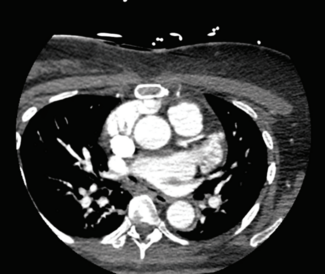

Phrenic nerve injury is a complication of all types of atrial fibrillation ablation. It is diagnosed based on symptoms and physical examination shortly after an electrophysiologic ablation.